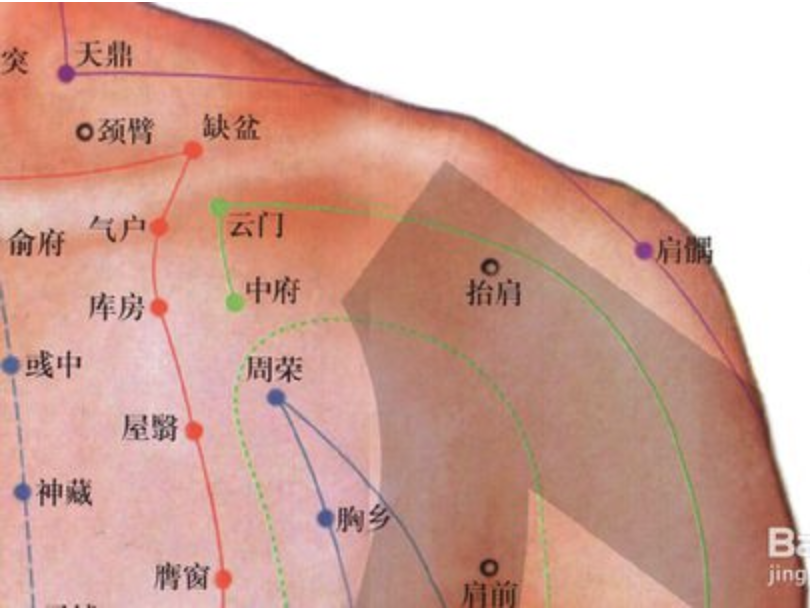

【(一)手太阴肺经(图10-19-1)】

图 10-19-1 手太阴肺经循行及常用腧穴

3、经脉循行 肺手太阴之脉,起于中焦,下络大肠,还循胃口,上膈属肺,从肺系横出腋下,下循臑(nào)内,行少阴心主之前,下肘中,循臂内上骨下廉,入寸口,上鱼,循鱼际,出大指之端;其支者,从腕后直出次指内廉,出其端。

即该经起自中焦,向下联络大肠,回过来沿着胃的上口贯穿膈肌,入属肺脏,从肺系(气管、喉咙)横行出胸壁外上方(中府),走向腋下,沿上臂前外侧,行于手少阴心经和手厥阴心包经的外面,至肘中(尺泽)后再沿前臂桡侧下行至寸口(桡动脉搏动处),又沿大鱼际外缘出拇指桡侧端(少商)。